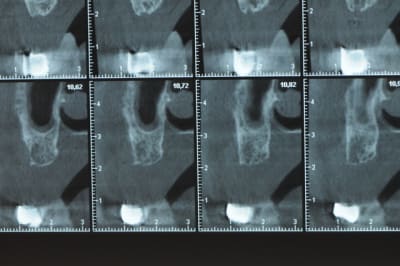

Une petite étude de ton cas D57

Sous réserves bien sur de voir l’animal en vrai

Les zones exploitables radiologiquement parlant:

Coupes implant

2,3 40100

4,96 35130 avec sinus lift mais difficile

5,25 35150

6,02 35130

6,78 35115 après réduction de hauteur de crête

7,26 35115 après réduction de hauteur de crête

8,51 35150

10,43 40115 ou 50115

11,10 40115

Ce qui nous fait 9 implants possible évidement avec un comblement de sinus on augmenterait encore les zones implantable mais ce n’est pas le but recherché, avec 8 (4+4) il doit être possible de faire une belle barre support de complet